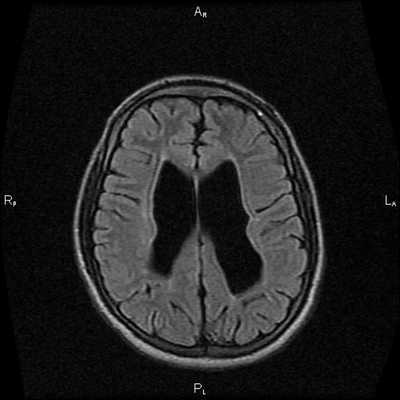

Пациентка Ш. 83 лет

Проблема: жалобы на снижение памяти, повышенную утомляемость. Пациентка была направлена на МРТ головного мозга с целью исключения различных патологий.

При МРТ головного мозга установлено: МРТ признаки хронической недостаточности мозгового кровообращения; выраженная открытая внутренняя гидроцефалия, свидетельствующая о признаках атрофических изменений в головном мозге.